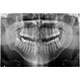

Size doğru bir diş analizi sağlayabilmek için dişlerinizin şu anki görünümünün fotoğraflarına ihtiyacımız var.

Resimlerinizi yüklemek için bir grafiğe tıklayın.